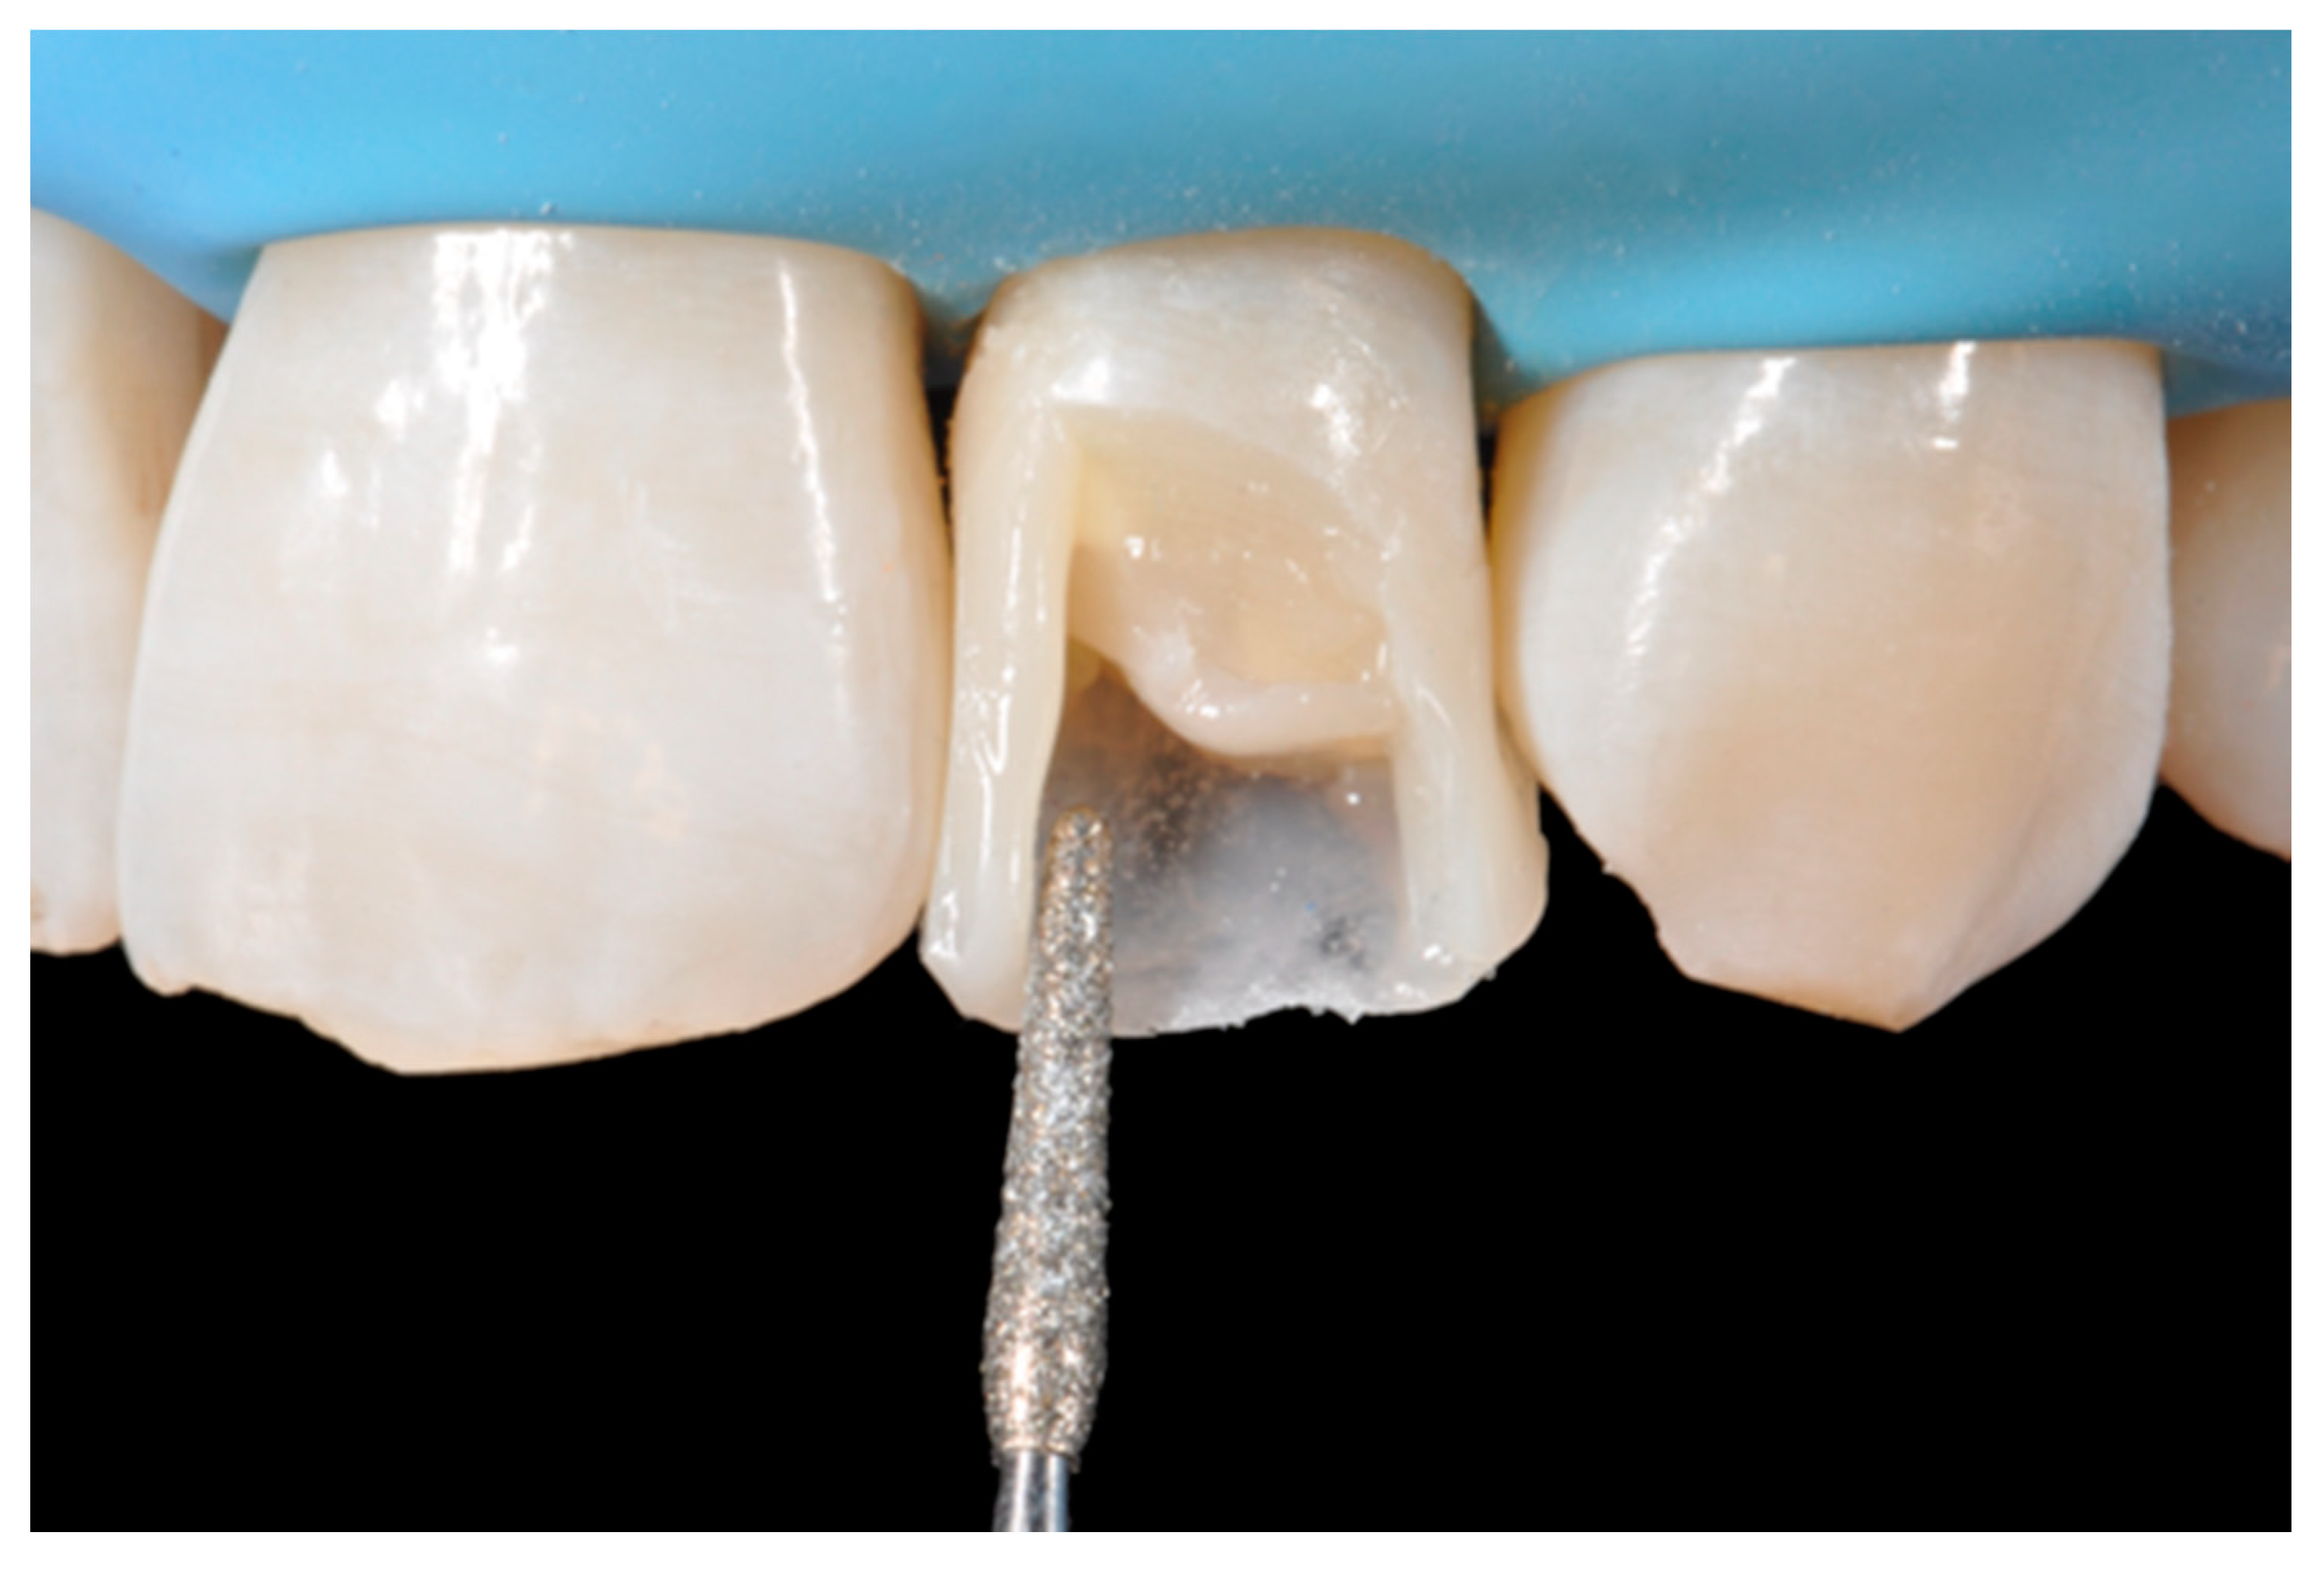

The internal ones can be reduced with diamond burs (WL 268 014 Horico, Berlin, Germany) (Figure 8).

Figure 8.

Excessive thickness of interproximal walls is reduced with a low-speed diamond bur. Reprinted from Restauri diretti nei settori anteriori, G. Paolone, S. Scolavino, © 2021, with permission from Quintessence Publishing Italy.